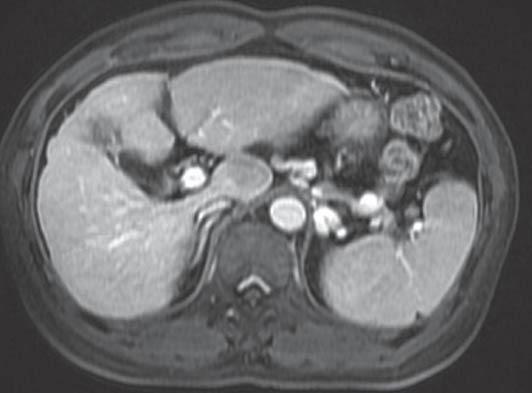

There were nine males and four females, age ranging between 30 and 72 years. The indications were hepatocellular carcinoma in nine patients, hilar cholangiocarcinoma in two, solitary fibrous tumor in one, and a regenerative nodule in one patient. Left-sided approach was employed in seven cases, right-sided approach in three cases and a combined approach in three cases. Operating time ranged between 125 and 225 min and blood loss ranged between 210 and 630 mL. There was no mortality in the post-operative period. No local recurrence was noted in the follow-up period ranging from 6 months to 7 years.

Caudate lobe resections, although technically challenging, can be successfully performed with minimal blood loss. Surgery offers potential cure in isolated caudate lobe tumors. The location and size of the tumor decides the approach.

有9例男性和4例女性,年龄在30至72岁之间。手术指征为9例肝细胞癌、2例肝门胆管癌、1例孤立性纤维瘤和1例再生结节。7例采用左侧入路,3例采用右侧入路,3例采用联合入路。手术时间在125至225分钟之间,失血量在210至630毫升之间。术后无死亡病例。在6个月至7年的随访期内未发现局部复发。

尾状叶切除术虽然在技术上具有挑战性,但可以在失血最少的情况下成功进行。手术为孤立性尾状叶肿瘤提供了潜在的治愈机会。肿瘤的位置和大小决定了手术入路。